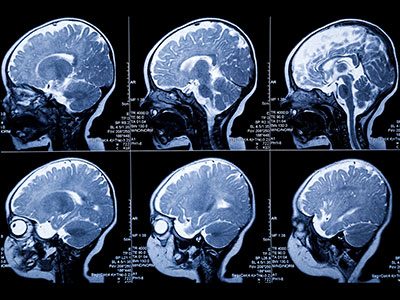

The Developing Brain Institute, directed by Catherine Limperopoulos, PhD, is housed in the Department of Diagnostic Imaging and Radiology and affiliated with the Prenatal Pediatrics Institute at Children’s National Hospital. Our research focuses on the developing brain in utero, after birth and through preschool. We are developing advanced magnetic resonance imaging (MRI) techniques to examine the structure, connectivity and metabolism of the brain in ways that cannot be done with conventional MRI studies. It is our long-term goal to be able to identify babies with impaired brain growth as soon as possible to facilitate more timely interventions and clinical planning.